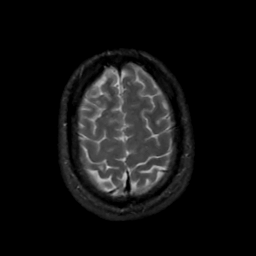

MR Study #12, May 12, 1991 -- Slice #42